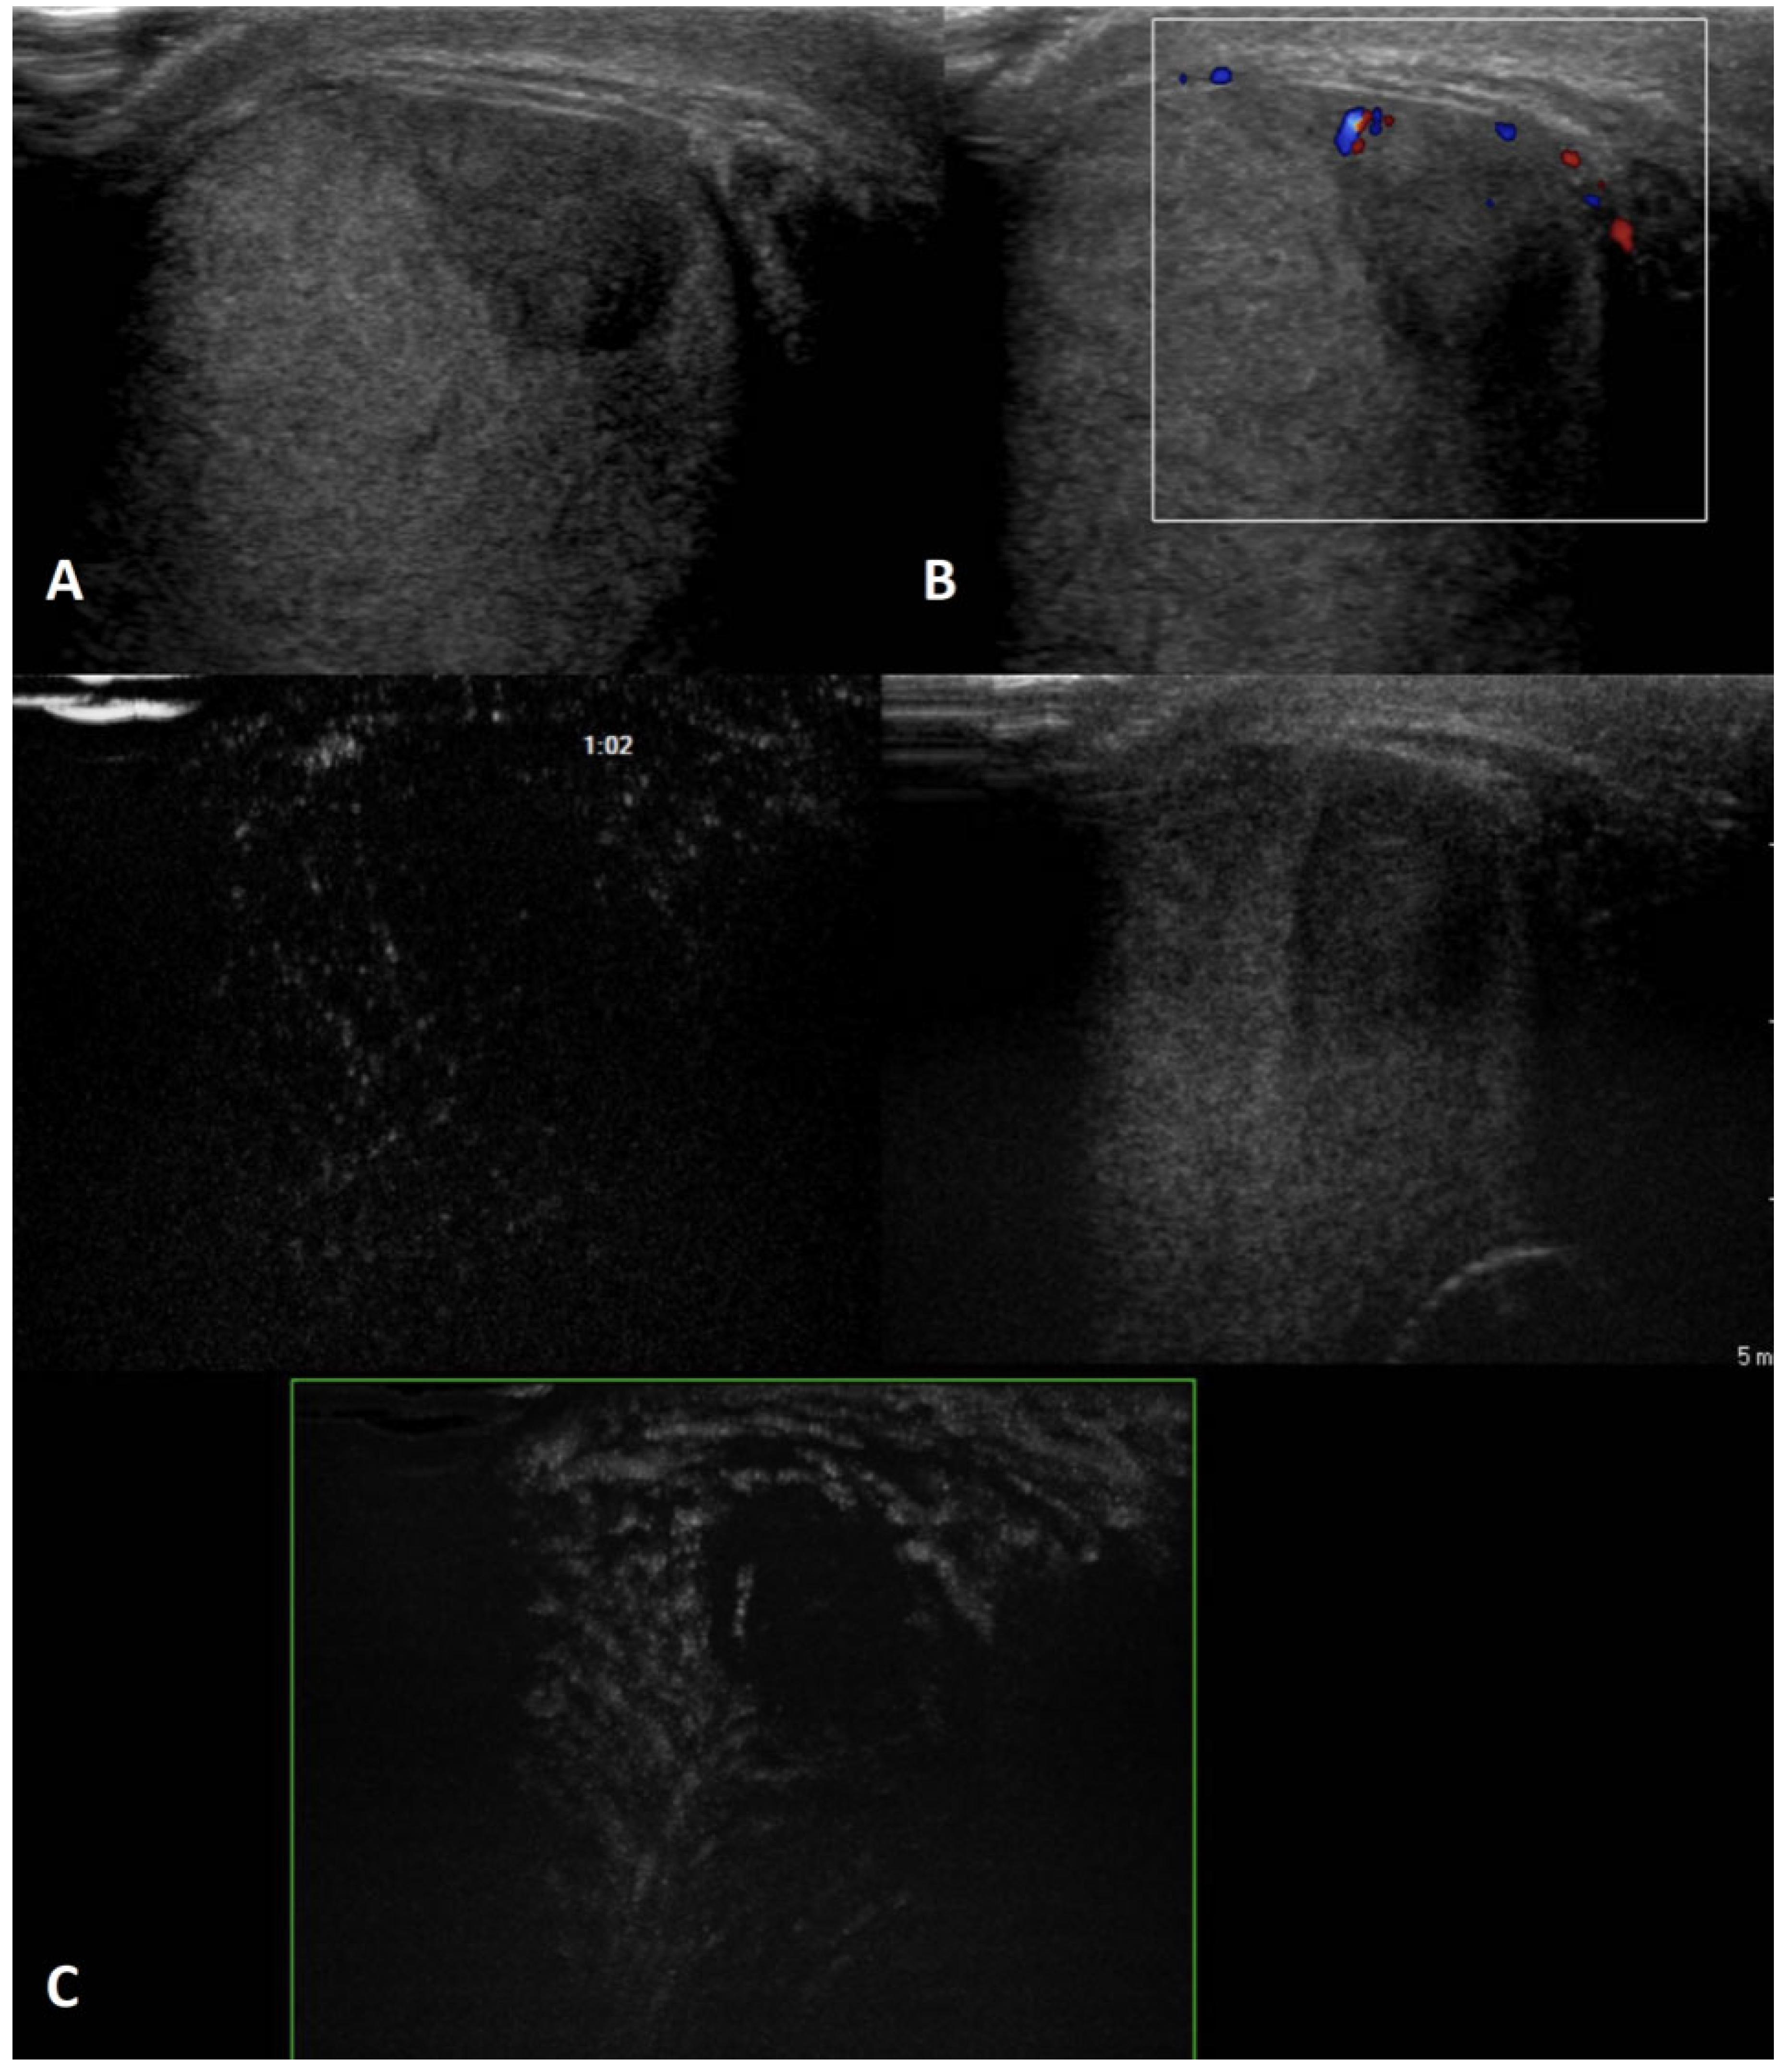

4.5. Segmental Testicular Infarction

| Segmental infarction | Idiopathic or consequent to surgery, inflammatory events, blood disorders or autoimmune diseases; usually acute painful swollen scrotum OR asymptomatic | Hypoechoic wedge-shaped or roundish area | Avascular OR peripheral rim of low CD | Unenhanced/ perilesional rim enhancement | Soft lesions with high elastic strain |